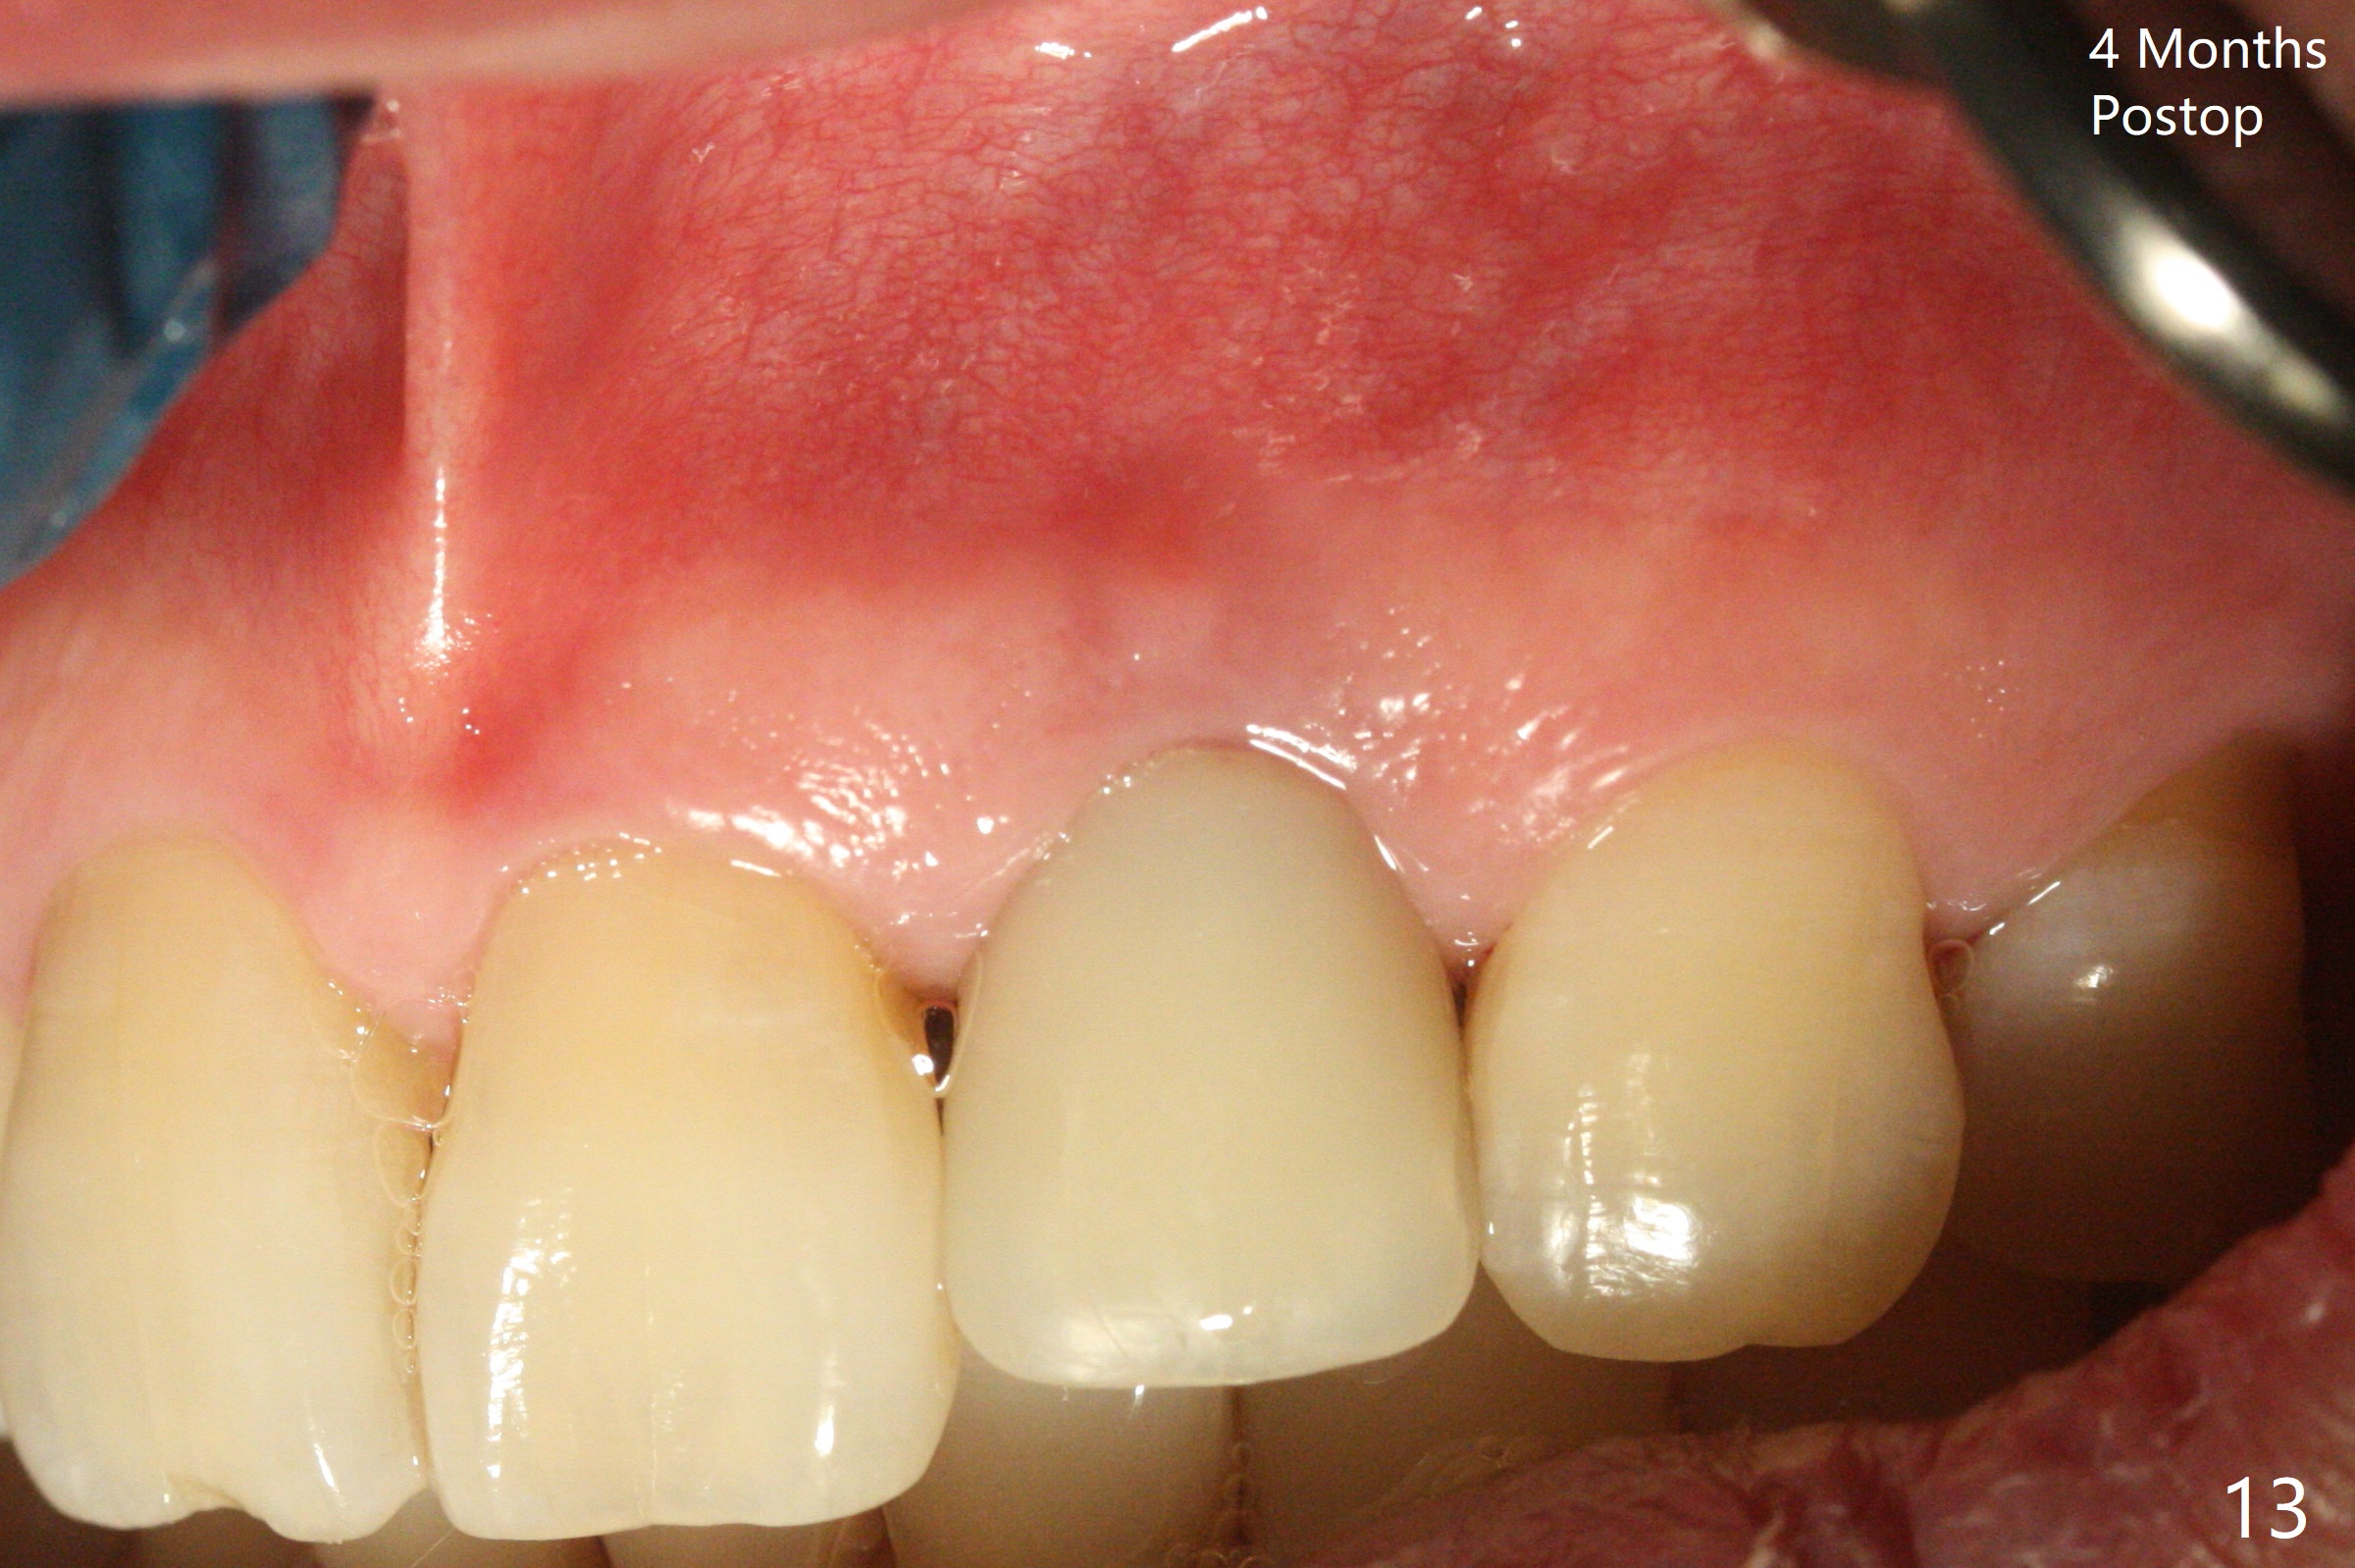

病人回来带来瘘道(图一),不过不会增加难度,病牙去除,它便自动消失。尽管颊侧骨壁完全失去,颊侧牙龈仍丰满(图二),为什么呢?第一,因为粗大牙根存在,第二两旁牙齿,牙槽骨撑着帐篷(侧切牙颊侧牙龈),第三,牙冠。为了防止术后牙龈塌陷,尽量不切开,即刻放置植体(牙根);由于前牙缘故,这次植体不能很大,所以植骨必须过度(over grafting),最后即刻制作临时牙冠,撑住牙龈。这就是所谓每个人进入角色。这个牙根有一种先天性畸形:dens in dent (图三(腭侧观):箭头)。尽管腭侧牙根畸形,腭侧骨壁吸收临床上并不严重,所以钻洞仍偏腭侧。当预定最后钻头还在钻洞时,填入大量粘性骨块(图四:*),细长植体还没有完全卡入鼻底(图五),最后好像可以(图六,七)。植体,骨粉入位(图八),最后临时牙冠出场(图九)。尽管植体小,术后一周临时牙冠仍然可以维持牙龈原有形状(emergency profile,图十:箭头(*:树脂强化牙冠固定))。图十一以不同角度显示瘘道缩小。术后三周取出有些松动的临时牙冠,骨粉虽然还没有被肉芽组织整合,但是显得正常,周围牙龈健康(图十二)。术后4个月牙龈形态正常(图十三),没有触痛;颊侧骨板轻度凹陷(图十四);骨粉仍在原位(图十五)。术后7个月骨粉仍在原位(图十五,十六,但是冠部密度减低(可能骨粉流失,需要牙周或者树脂敷料保护)),没有螺纹暴露。但是牙冠边缘暴露,说明牙龈收缩(图十七,与图十三对比),颊侧骨板仍塌陷(图十八)。插入龈线取得多个目的:修整基台边缘,取模,颊侧牙龈推向颊侧,有利于即将衬里牙冠龈缘进入龈下(图十九)。取模后牙冠边缘(图二十:<)衬里,然后修整,变窄,以便插入龈下,促进颊侧牙龈下降(图二十一,二十二)。术后8个月牙冠粘固前牙龈健康(图二十七,八),牙冠(图二十九)固位后,病人满意(图三十),咬合调整(图三十一),注意腭侧粘固粉流出通道(<)。